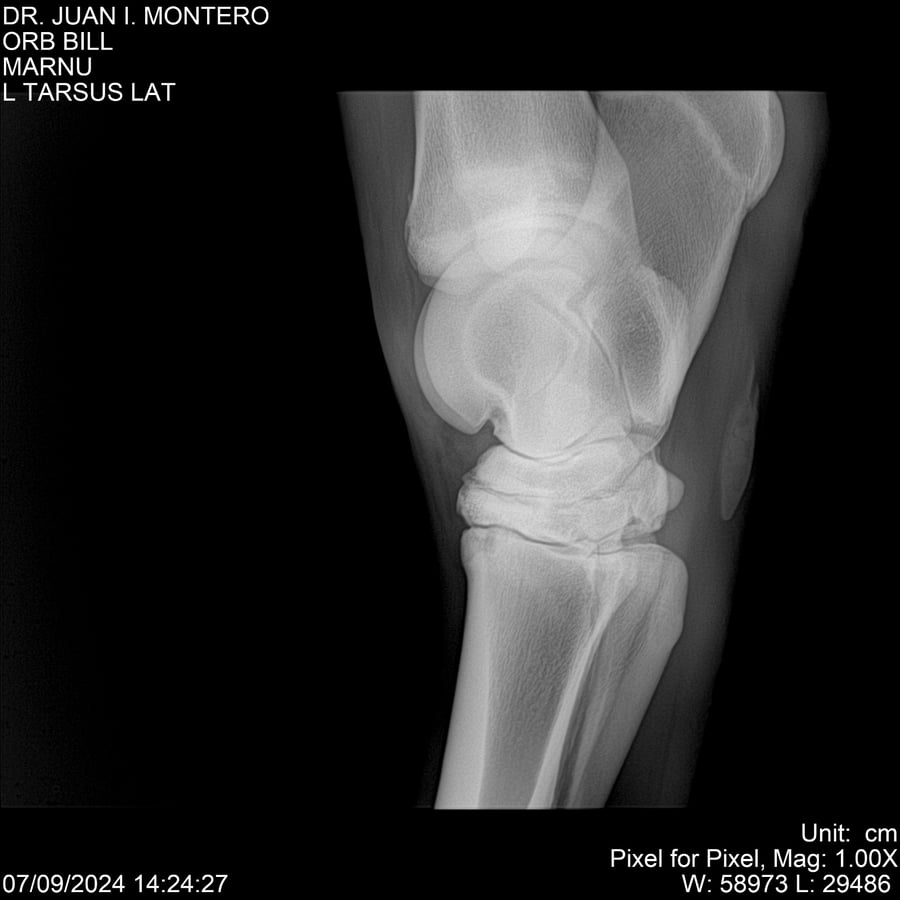

LOTE 7, ORB BILL 🔥 🔥 🔥 Lote Anterior Volver al remate Lote Siguiente Ficha Contacto Montevideo - Ficha del Lote Identificador: #282523 Categoría: Yeguarizos Montevideo - 83 Visualizaciones ClicData Contacto Empresa: Abelenda N. R., Walter Hugo Nombre*: Teléfono* : E-mail* : Mensaje Enviar Registrese gratis Este contenido Exclusivo está disponible sólo para usuarios registrados Ingresar